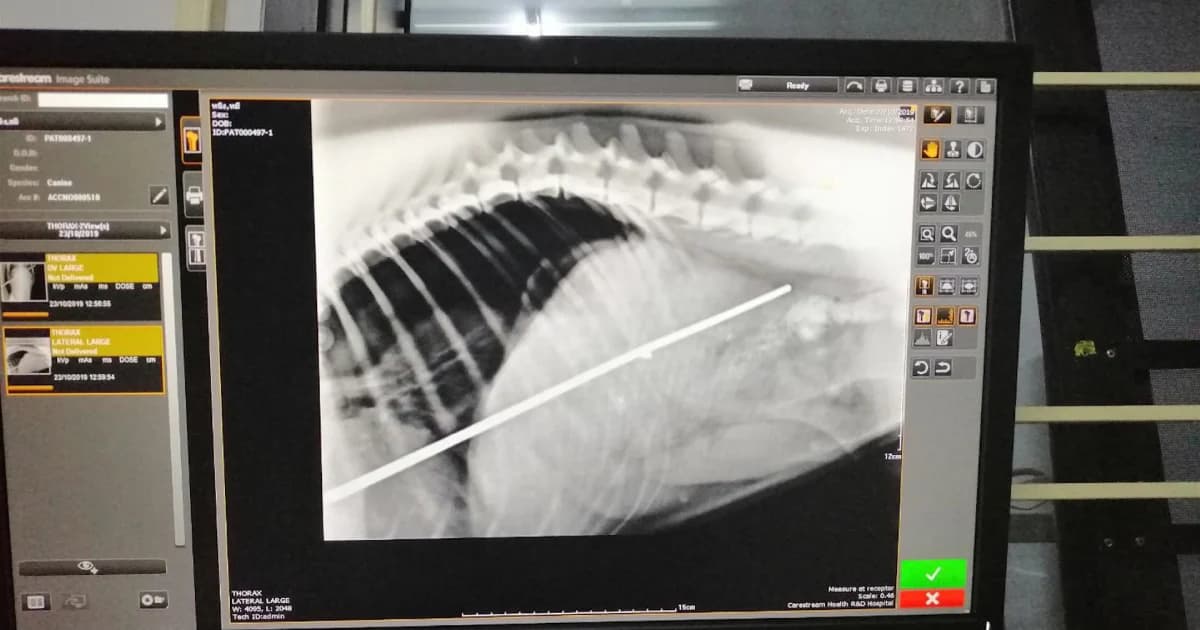

ด้านสัตวแพทย์ระบุว่า จากการตรวจพบว่า ฉมวกได้แทงทะลุตับ, กระเพาะ, กระบังลม และลำไส้ อาการน่าเป็นห่วง แต่หลังจากที่ได้ทำการผ่าตัด สุนัขตัวนี้ก็ปลอดภัยแล้ว สามารถเดินได้และอยู่ระหว่างการพักฟื้น ทั้งนี้ได้ตั้งชื่อให้มันว่า “เจ้าหมีดำ”